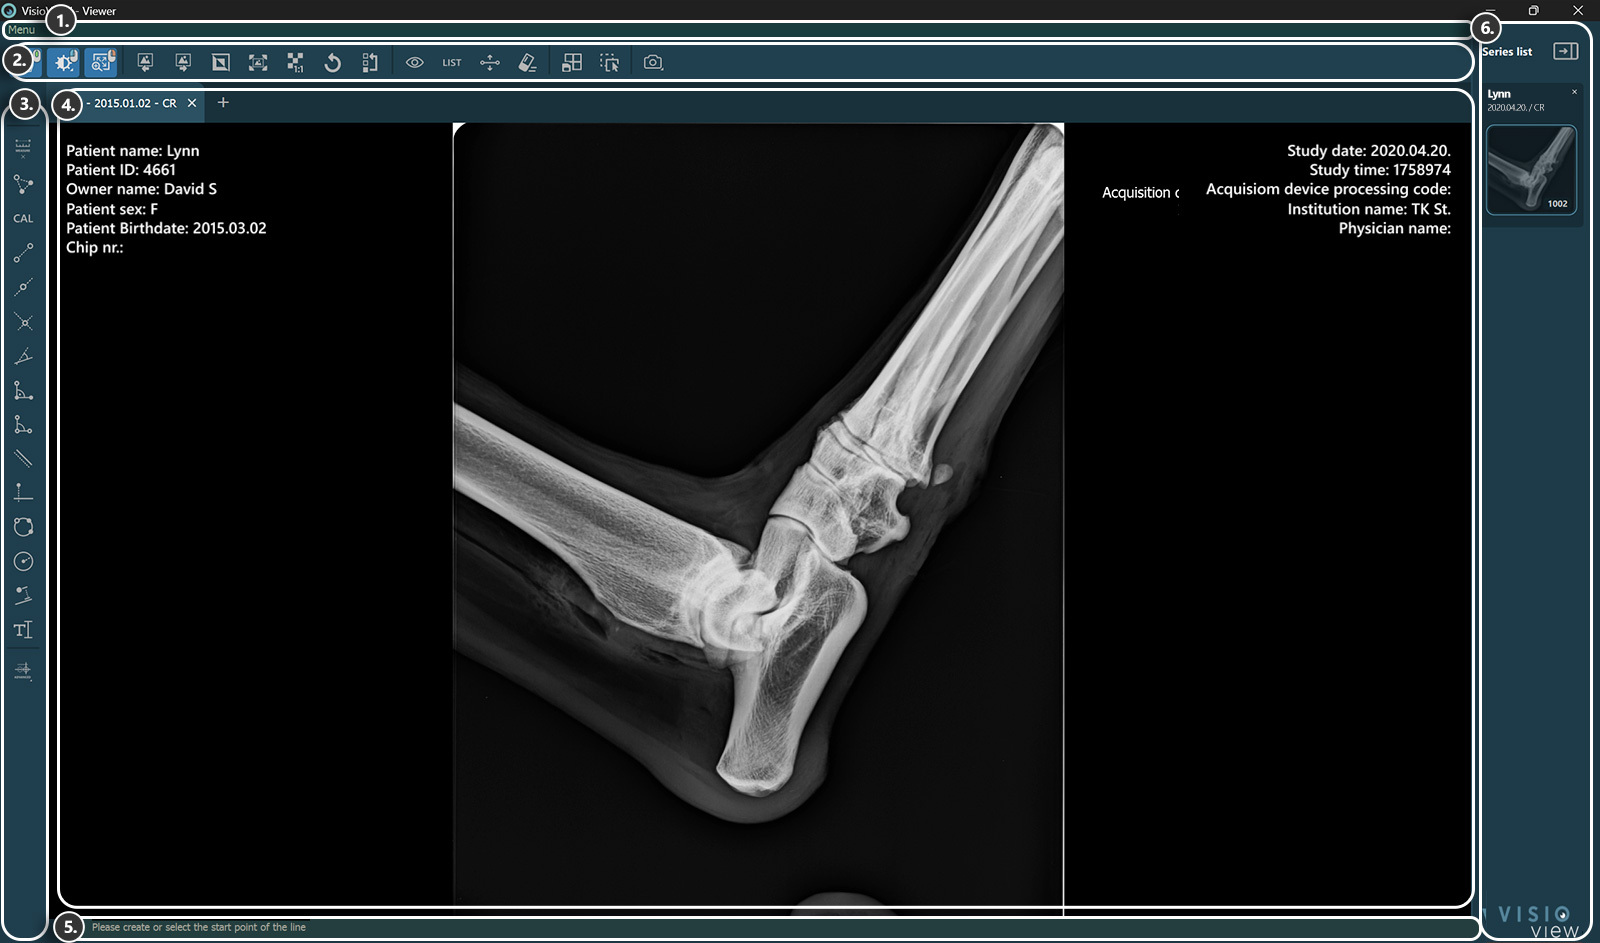

Sections of the VisioVIEW Viewer

The VisioVIEW Viewer consists of several sections, each tailored to a specific purpose. Below is a detailed description of each section.

../_images/image16.jpg

1. Menu Bar

2. Top Toolbar

3. Left Toolbar - Measurements

4. Viewer Area

5. Information Bar

6. Study Information & Series Panel